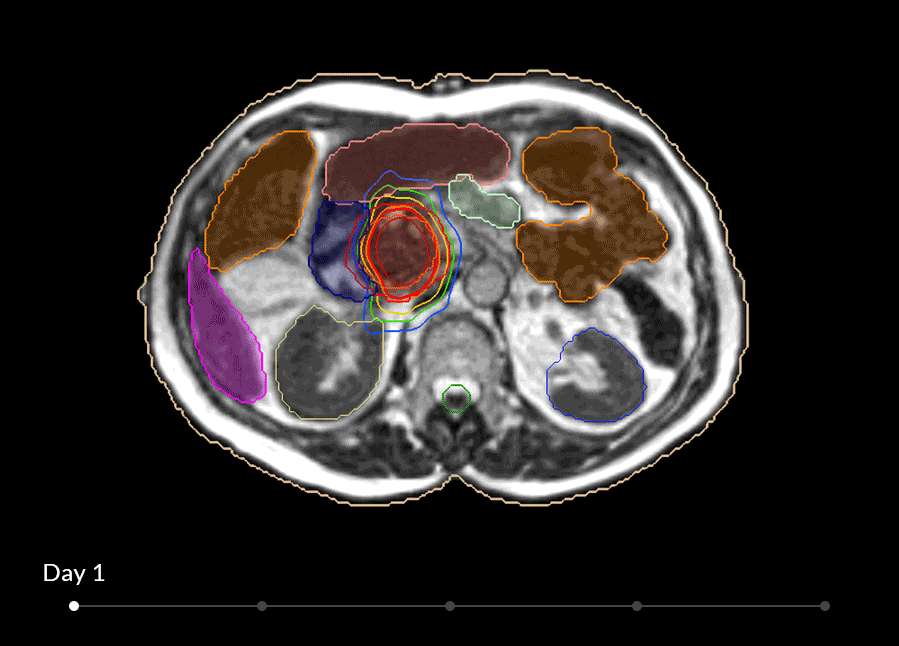

MRIdianは照射中でも、常にMRI画像を見ながら照射することが可能になりその画像を用いて、腫瘍の位置や形を確認し、治療計画の確認・変更することができ、アダプティブ放射線治療までシームレスに行えます。

既存のワークフローを妨げることなく、MRI画像は高速で表示され、腫瘍と周辺機器、リスク臓器をリアルタイムに観察し、治療期間中は常にその変化について視覚で捉えることができます。